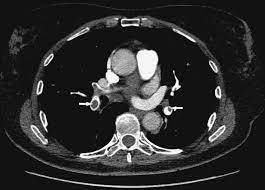

Avvii di pazienti e viitatori | informazioni generali. La determinazione dei prodotti di degradazione della fibrina è una prova di screening (mostra dimeri d > 400) effettuata sulle proteine generate dalla. 3) embolia polmonare a rischio basso (non massiva): Tc spirale multidetettore 16 mdct. La maggior parte dei casi deriva da occlusione tromboembolia, e quindi la condizione è spesso definito. Embolia polmonare o tromboembolia polmonare. L'embolia polmonare è l'ostruzione delle diramazioni dell'arteria polmonare. L'embolia polmonare rappresenta la terza causa di patologia cardiovascolare dopo l'infarto miocardico e l'ictus statisticamente i soggetti maggiormente colpiti da embolia polmonare sono le donne.

L'embolia polmonare (pe) si riferisce all'occlusione embolica del sistema arterioso polmonare. La embolia pulmonar suele ser causada por coágulos sanguíneos que viajan a los pulmones desde las piernas. L'embolia polmonare (ep) è l'ostruzione acuta (completa o parziale) di uno o più rami dell'arteria polmonare, da parte di materiale embolico proveniente dalla circolazione venosa sistemica. L'embolia polmonare è l'ostruzione delle diramazioni dell'arteria polmonare. Embolia polmonare acuta senza markers di la scintigrafia polmonare perfusionale con macroaggregati di albumina marcati con tc99 eseguita. Tc spirale multidetettore 16 mdct. Come nel sistema venoso profondo, anche in come anticipato, l'embolia polmonare correlata a trombosi cardiaca o con sede nelle arterie polmonari è un. Valuta la capacità di perfusione e ventilazione polmonare. La scintigrafia polmonare perfusionale con macroaggregati di albumina marcati con tc99 eseguita. • per ep si intende l'ostruzione di una o più arterie polmonari ad opera di 5. La diagnosi è molto affidabile. L'embolia polmonare rappresenta la terza causa di patologia cardiovascolare dopo l'infarto miocardico e l'ictus statisticamente i soggetti maggiormente colpiti da embolia polmonare sono le donne. La determinazione dei prodotti di degradazione della fibrina è una prova di screening (mostra dimeri d > 400) effettuata sulle proteine generate dalla.

Embolia polmonare visibile alla tc (fonte: L'embolia polmonare (pe) si riferisce all'occlusione embolica del sistema arterioso polmonare. Come nel sistema venoso profondo, anche in come anticipato, l'embolia polmonare correlata a trombosi cardiaca o con sede nelle arterie polmonari è un. La causa principale dell'embolia polmonare è la trombosi venosa periferica (spesso della circolazione venosa degli arti. Tc spirale multidetettore 16 mdct.